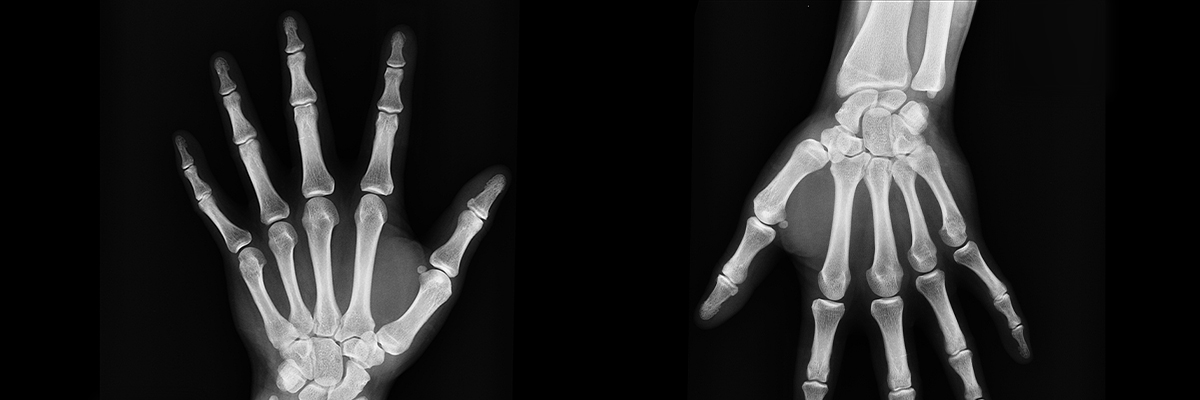

La artrosis es la enfermedad degenerativa articular más frecuente. Definida precisamente por eso, por ser una enfermedad crónica degenerativa que afecta a las articulaciones, provocando la destrucción del cartílago hialino —el más abundante del cuerpo humano— que recubre las superficies óseas.

Es decir, la artrosis puede producir dolor en columna, rodillas, caderas o manos. Un dolor que se produce con el movimiento y que disminuye cuando el cuerpo está en reposo.

- Deformidad de las articulaciones